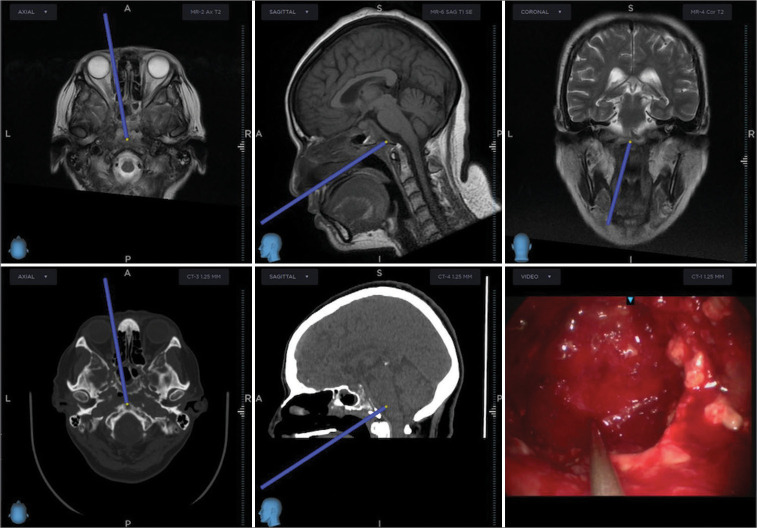

Given the MRI findings, surgical excision through navigation-guided transnasal transclival endoscopic extended approach and later nasoseptal pediculated flap rotation was performed, [Figure 4]. Transoperative findings showed sphenoidal rostrum lysis with extension to lateral recesses, clival, and sella turcica osteolysis, with no dural invasion. Surgical debridement was performed in a conventional manner, with no apparent complications. The patient was discharged 48 h postsurgery, with no clinical signs of transnasal fistula.

Figure 4:

Navigation-guided transnasal transclival endoscopic extended approach with clival drilling.